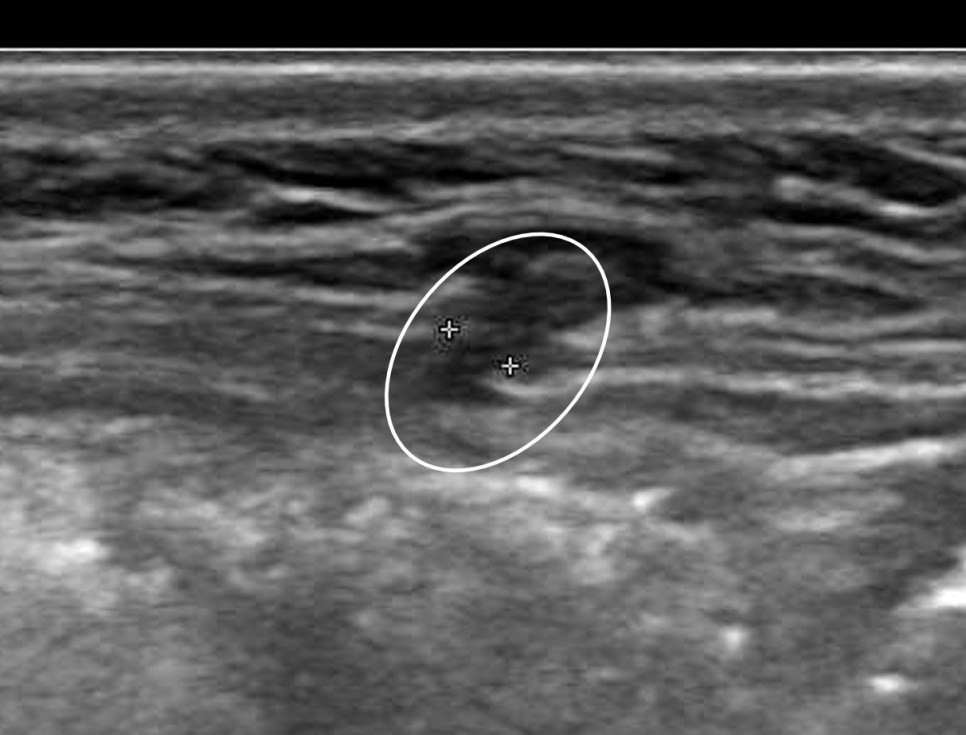

사진1. 복벽탈장 초음파사진 (주위보다 검은 부분이 닫히지 않은 구멍이다)

전신 마취가 필요하므로 전신 마취에 적합한지 확인하기 위한 기본적인 혈액 검사와 심전도, 흉부 엑스레이 검사를 실시합니다. 초음파검사를 실시할 수도 있습니다. 환자의 다른 병력에 의해 진단이 확실한지, 다른 진단의 가능성은 없는지, 수반되는 다른 질환은 없는지 확인하기 위해 초음파 검사를 실시합니다.